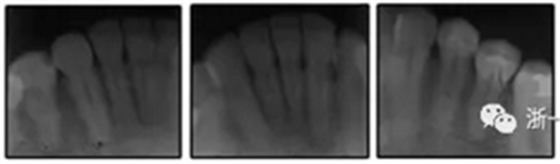

患者是一名39歲的白人婦女,病史不明。她主訴是她的右側(cè)顳下關節(jié)有不適癥狀,并希望改善她的笑容。她有一個對稱的臉型和一個II類2分類的微笑。她的側(cè)貌是凸的,90°的鼻唇角和骨性下頜骨發(fā)育不足??趦?nèi),上頜中線與面部重合,但下頜中線向右側(cè)偏移5mm;存在6mm的深覆蓋。她的兩側(cè)都是I類磨牙關系,左側(cè)是I類尖牙關系,右側(cè)是完全的II類尖牙關系。下頜右側(cè)第二前磨牙先天性缺失(圖1和圖2)。最初的全景片顯示了足夠的骨質(zhì)水平和全部的第三磨牙(圖3)。治療前的頭影測量片片和相應的頭影測量圖(圖3)證實ANB為7°,Wits評估為6 mm的骨性II類錯合(表)。上頜切牙相對與面部和顱底的位置很好。下頜切牙前傾。診斷為II類2分類錯合畸形,伴有骨性下頜發(fā)育不足,右側(cè)顳下頜關節(jié)癥狀,下頜中線向右側(cè)偏移5mm,先天性右下第二前磨牙缺失。

圖3. 治療前頭影側(cè)位片,頭影測量描跡圖和全口X光片